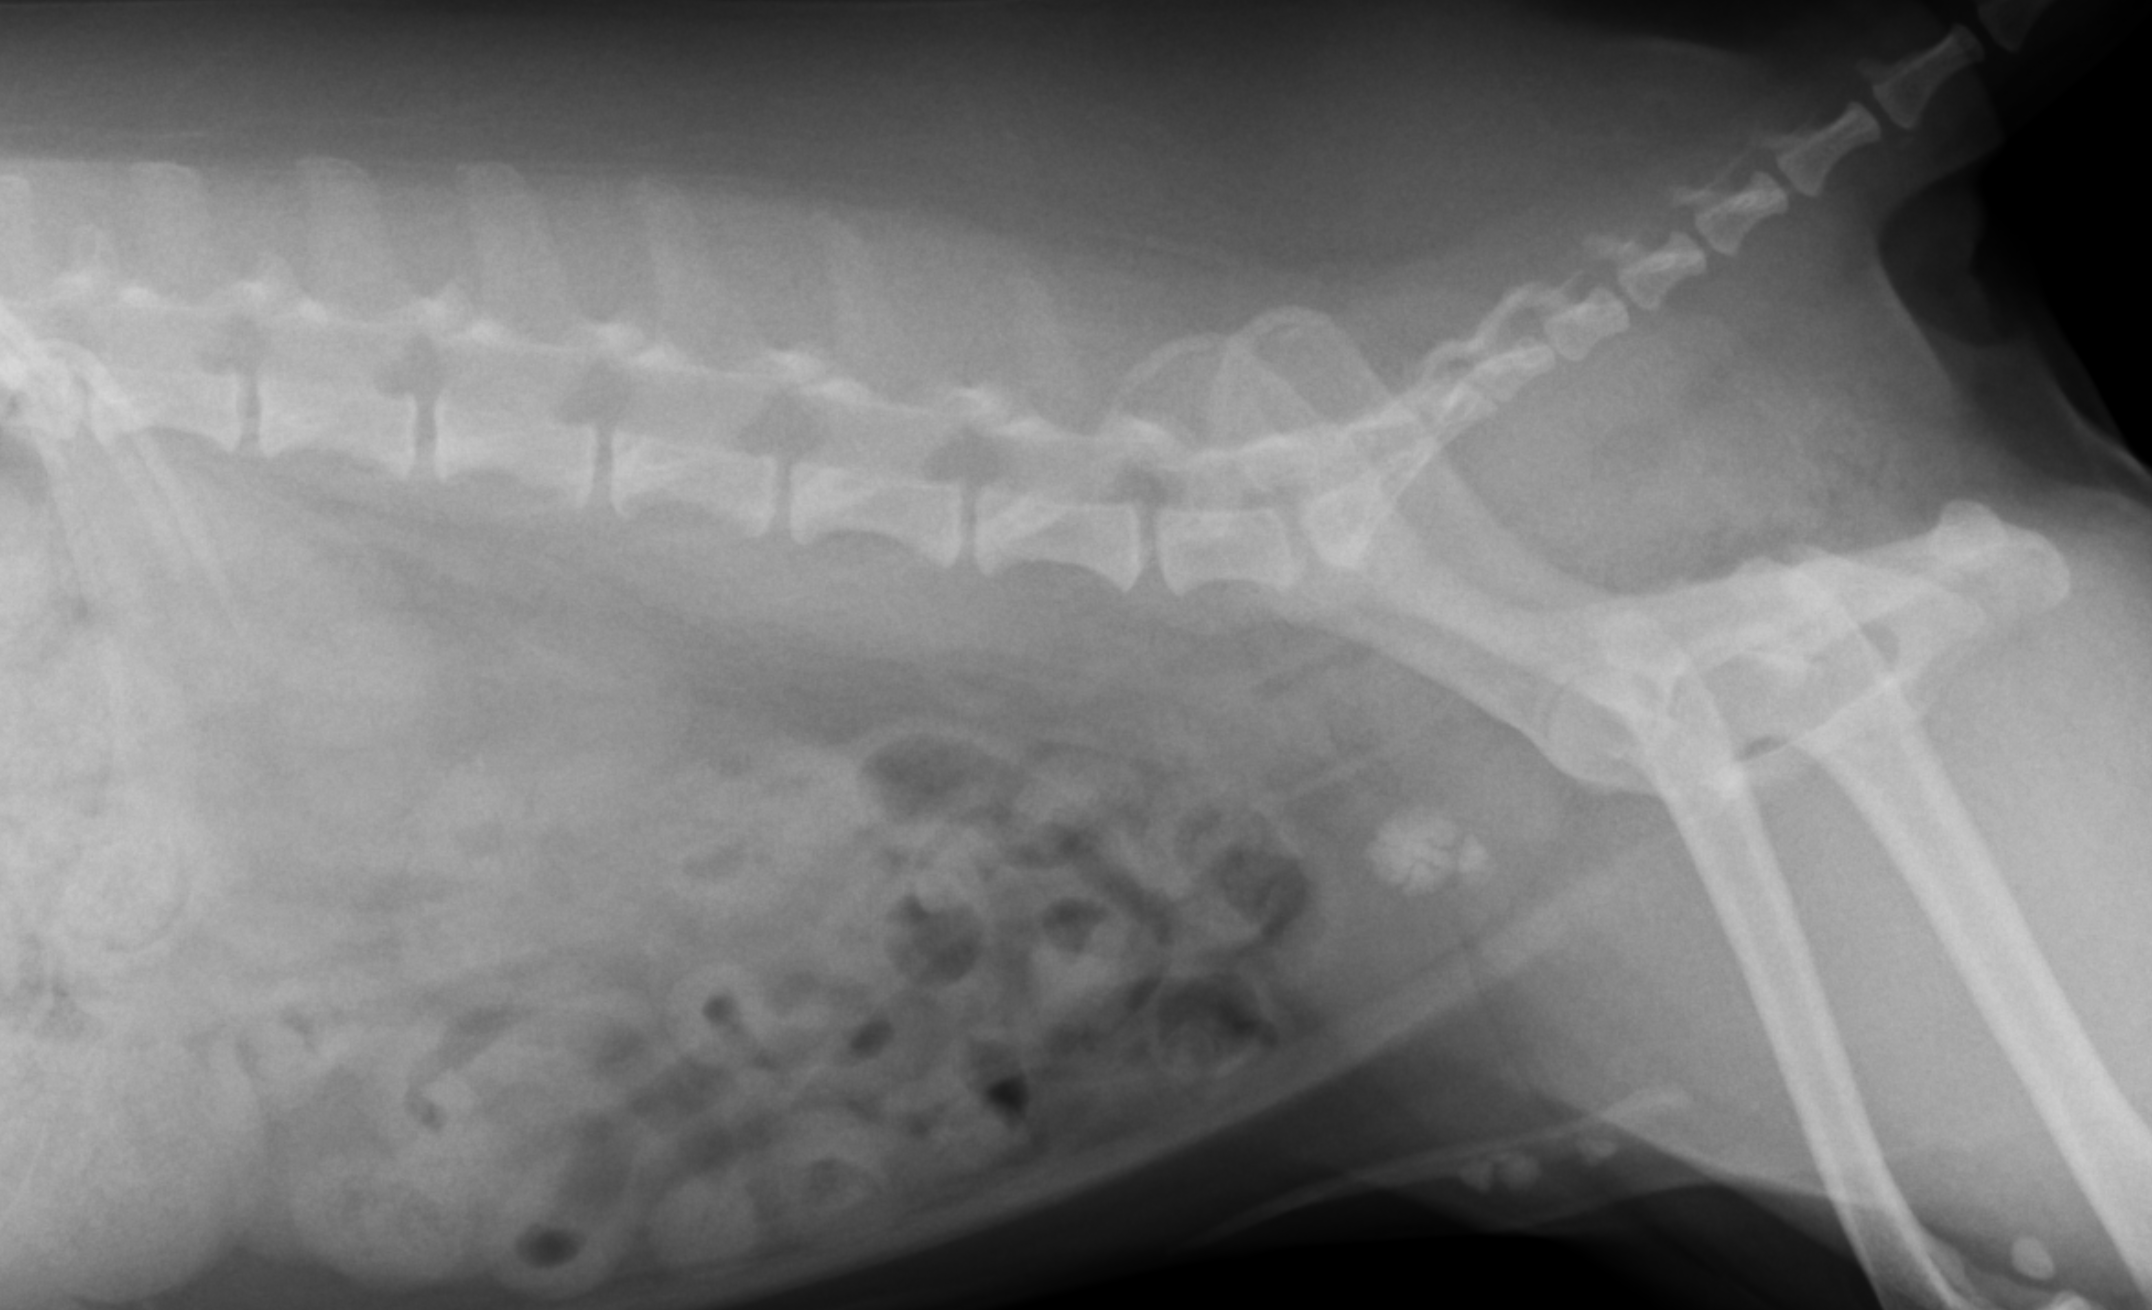

膀胱結石の検査はX線がメインですが、中にはX線に写らない石があるので、超音波と組み合わせて診断をすることになります